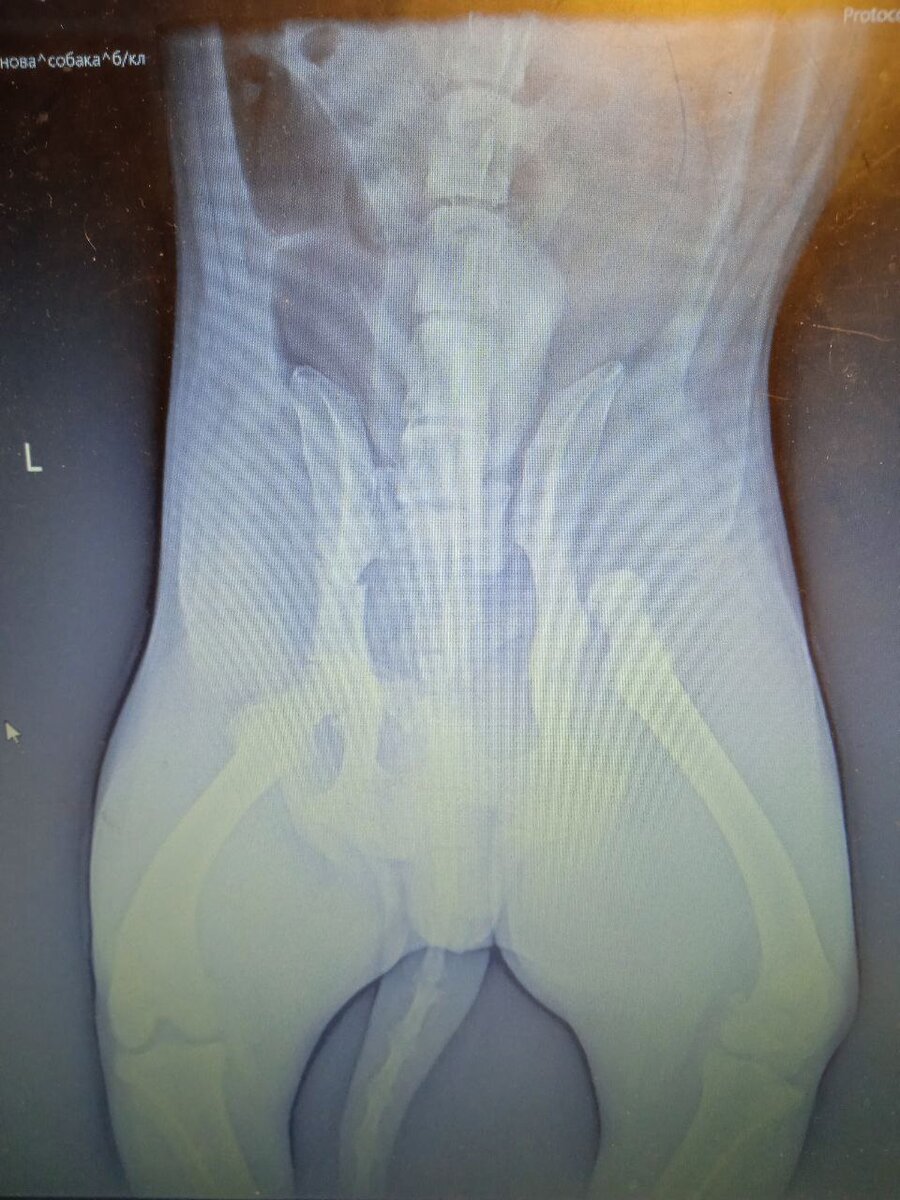

Вначале этого декабря возле рынка, был найден пёс, которого сбила машина. Рентген показал что у него перелом левой подвздошной кости, вывих правого ТБС, отрыв правого крестцового позвоночного сочленения. Назвали Герц. Сегодня будет операция. Мальчик очень добрый и терпит все манипуляции с ним очень стойко. Просим помощи в передержке, в погашении долга по клиники, ему нужен второй шанс! Помочь домашним мини-приютам Донбасса из блога #Мими_кися вы можете привычным способом, как и раньше - просто нажав здесь

Вначале этого декабря возле рынка, был найден пёс, которого сбила машина.

Рентген показал что у него перелом левой подвздошной кости, вывих правого ТБС, отрыв правого крестцового позвоночного сочленения.